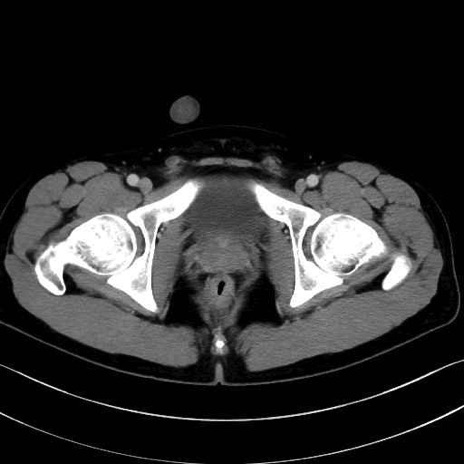

大腿方形筋(Quadratus femoris muscle)のCT画像の解剖

3. 殿部の筋肉(表層・中層・深層)

大殿筋 (Gluteus maximus)

中殿筋 (Gluteus medius)

小殿筋 (Gluteus minimus)

4. 深層外旋六筋(股関節の深部)

大腿方形筋 (Quadratus femoris)